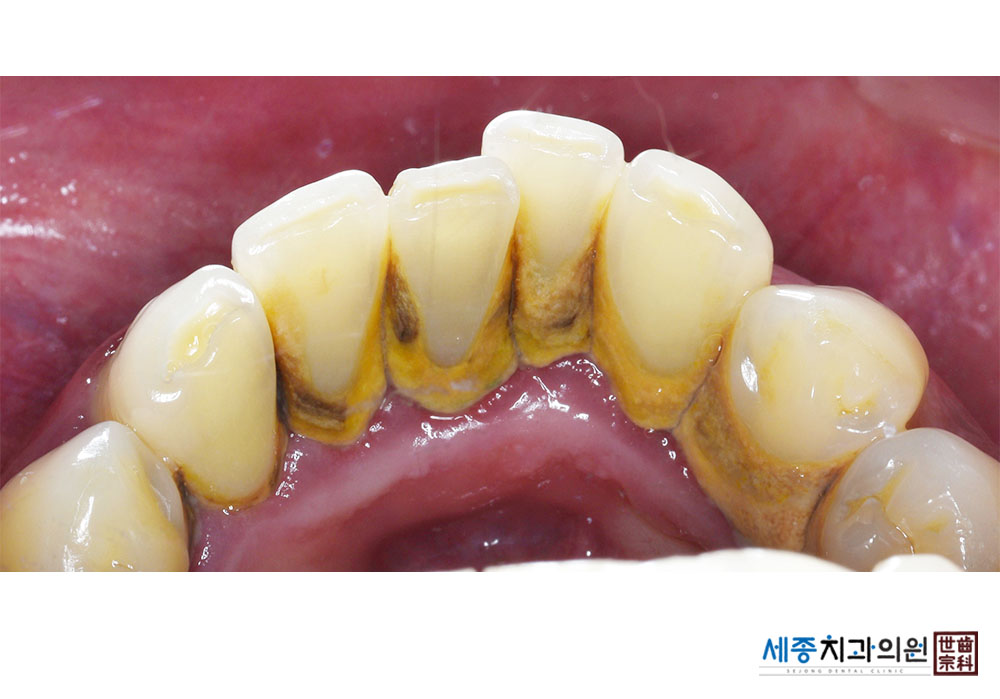

[스케일링] 치주질환 예방 스케일링

치료전 : 2019-04-01

가글마취&저주파 스켈러를 사용한 착색제거 스케일링